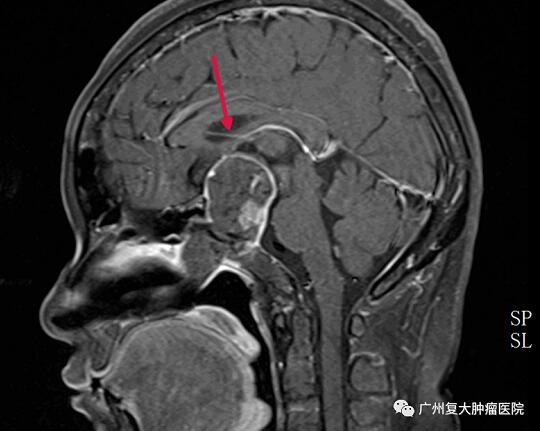

术后

因为肿瘤巨大,呈侵袭性生长,往往对周围解剖结构造成破坏,毗邻结构复杂,手术难度大、风险高。且患者不接受开颅手术,经专家团队反复讨论,我院决定为包姐实施微创手术——经鼻垂体瘤切除术。术后,患者病情稳定,视力较术前明显好转,住院一段时间后也康复出院。